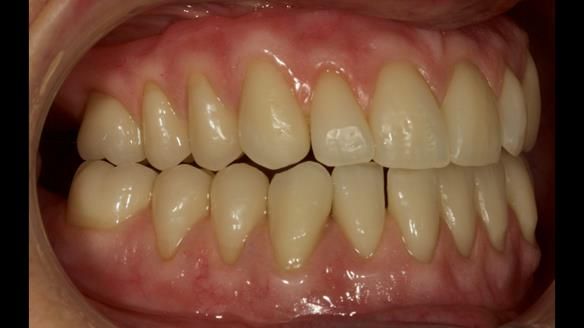

This newsletter describes in step by step detail the provision of a lower implant supported metal based complete denture with three dental implants positioned in the anterior mandible. The upper arch was restored with a metal based complete upper denture.

This 72 year old woman (Mary) was referred to me from her general dental practitioner from Ireland.

Mary had 3 dental implants placed in the anterior mandible 10 years previously with new complete dentures. These were successful for a time. The dentures were replaced a few years later. Mary was never pleased with the new lower denture as they did not fit the implants properly. This patient was referred to me from Ireland, to my practice in Garstang, England.

Diagnoses of the complete dentures

- Locator attachments not engaging the housings in the lower denture.

- Suboptimally shaped dentures with poor tissue fit resulting in rocking of the dentures.

- Bland aesthetics.

I provided new metal based complete dentures. The clinical situation and treatment process is shown in detail below with photographs. I provided the clinical work and Rowan Garstang provided the technical work. The dentures took 5 visits to make - with the patient travelling by plane from Ireland to Manchester. The patient had one review after the dentures were fitting.